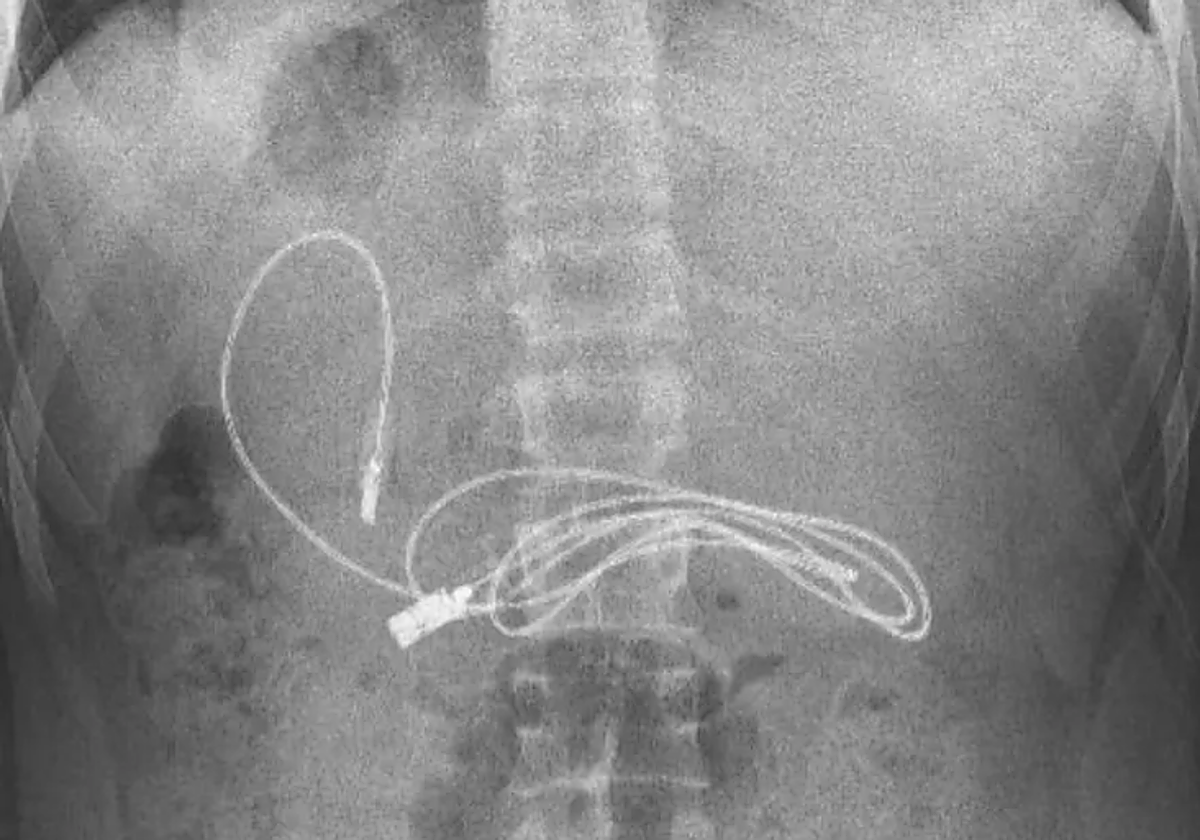

Un adolescente de 15 años desconcertó a los médicos cuando ingresó en un hospital con un cable de carga USB, que parecía encajar tanto en teléfonos como en auriculares, alojado en sus entrañas, informó 'The Mirror'. El niño, de Diyarbakir, Turquía, fue llevado ... a urgencias por su familia después de quejarse de náuseas y dolores de estómago. Una radiografía reveló rápidamente la pesadilla recubierta de plástico que esperaba la digestión.

El paciente fue trasladado a tres horas de distancia, al Hospital de la Universidad de Firat en Elazig, donde un especialista se encargó de su caso. El gastroenterólogo pediátrico Yasar Dogan realizó un procedimiento con endoscopia para librar al niño del cable.

«Obviamente tuvimos dificultades para quitar el cable, ya que un extremo del cable había pasado al intestino delgado», explicó Dogan. Tras sacar el cable enrollado, que resultó tener un metro de largo, también se descubrió una cinta para el cabello dentro del niño.

No está claro cómo o por qué se tragó los objetos. «Después de que el procedimiento concluyó con éxito, el paciente fue enviado a casa con buena salud», agregó Dogan.